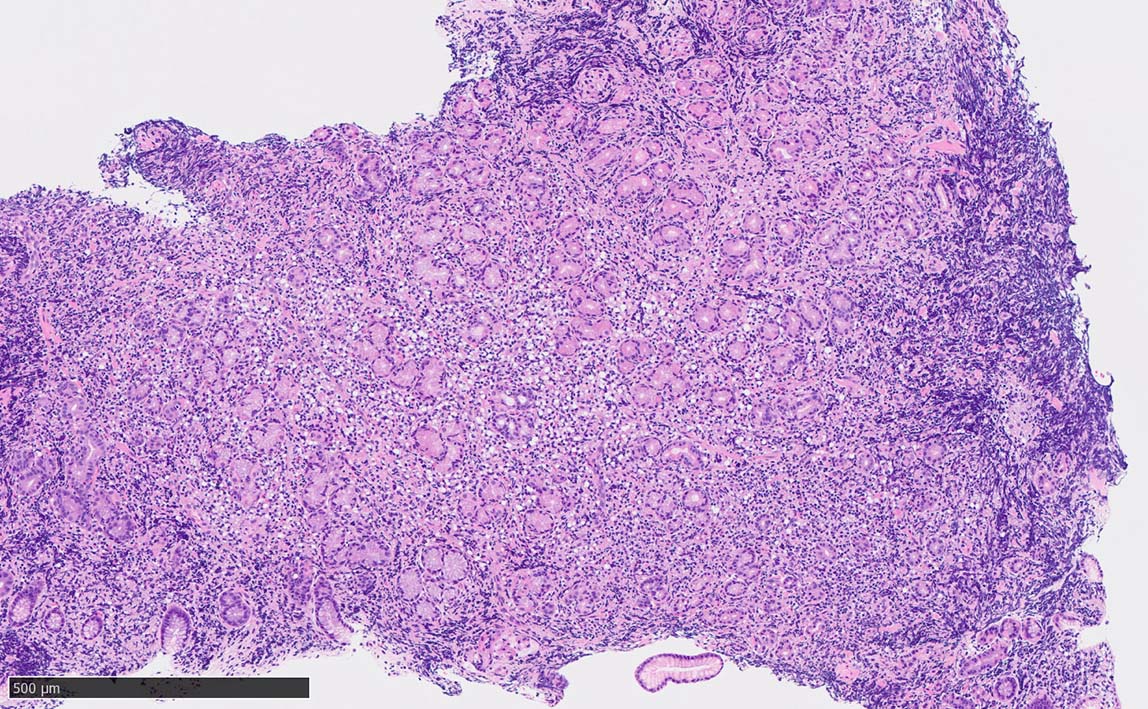

Signet-ring cell lymphoma of the stomach

60 year-old male. 胃生検組織

stomach biopsy, HE

非結節部位

固有腺のLEL様所見